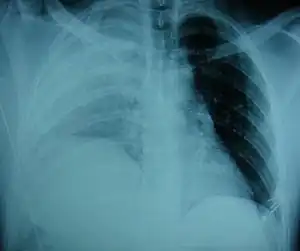

| An X-ray showing a raised diaphragm on the right due to a rupture of the diaphragm on that side.[1] | |